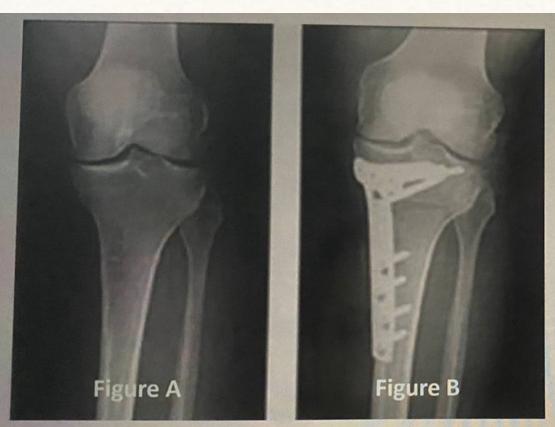

Q9: A 45-year-old male complained of left knee pain for 3 years that didnโt improve with conservative treatment. His x-ray is shown in Figure A. He underwent the procedure, as seen in Figure B. What is the aim of this procedure?

- B. Redistribute the patientโs weight.